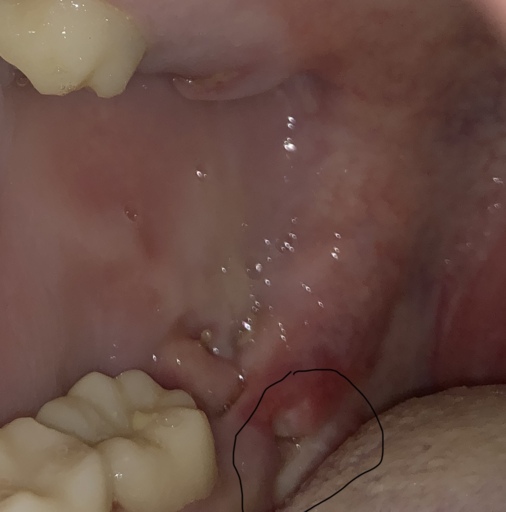

Is the a dry socket or normal healing?

got pulled 3 days ago curious whether or not it’s a dry socket isn’t into much pain I would really appreciate if someone would answer. feels normal just wondering has stitches around it. not to deep of a hole.